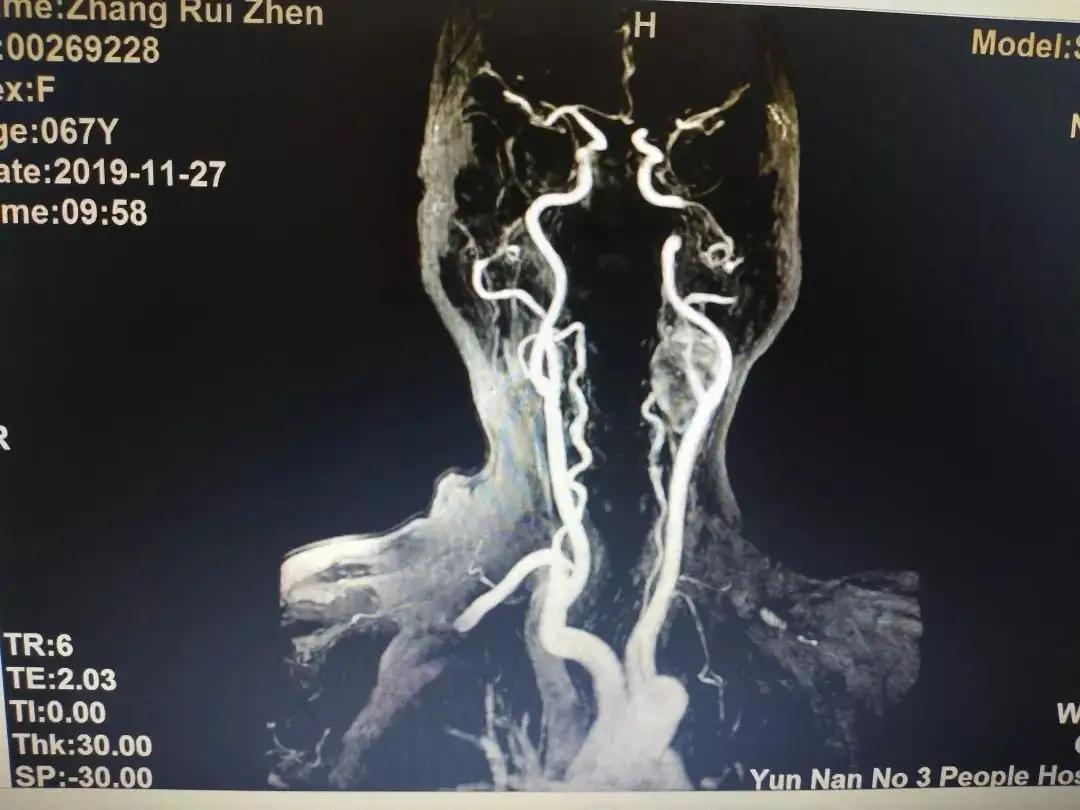

放射医学主要研究电离辐射对人体的作用、损伤与修复等方面的基本知识和技能,进行放射诊断、放射治疗、放射损伤的修复等。例如:使用X光机、CT等进行放射诊断,利用放射线进行肿瘤治疗,辐射损害的诊断与治疗等。